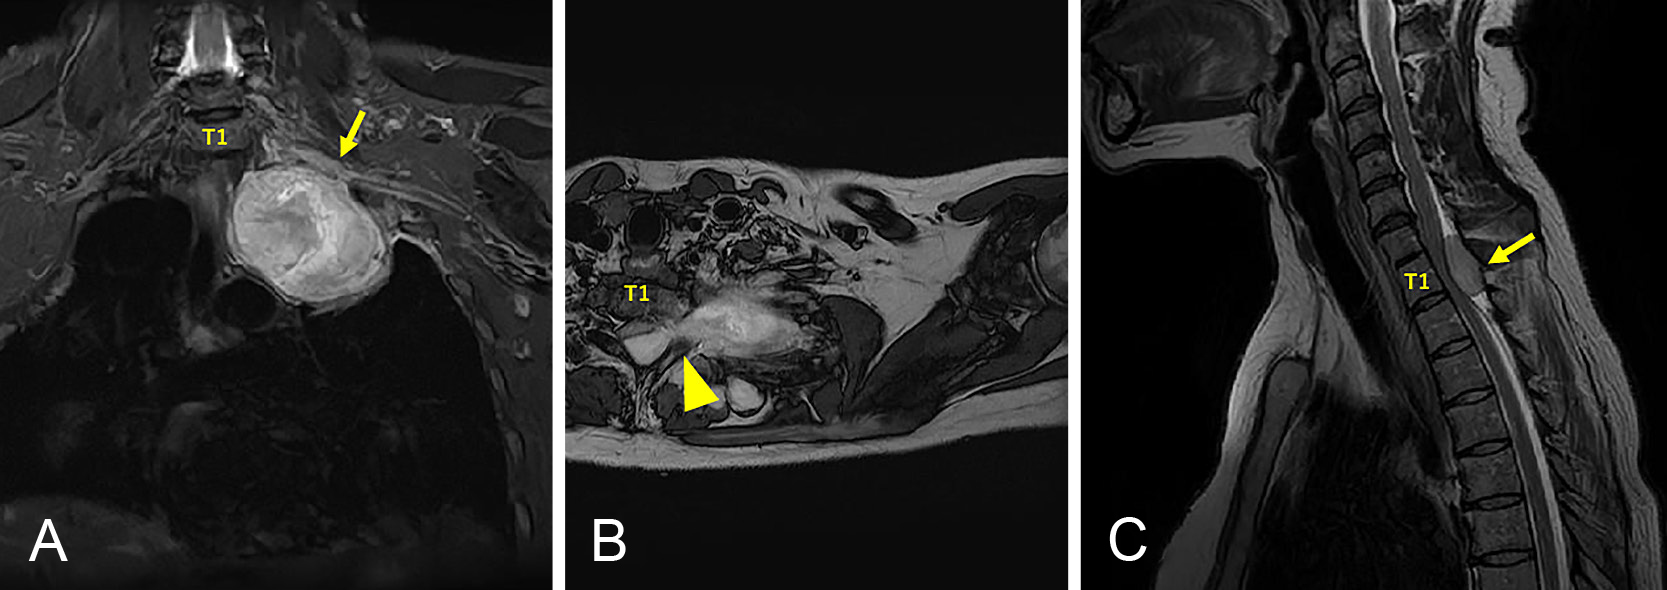

A case of myelin oligodendrocyte glycoprotein antibody-associated disease presenting with radiculopathies

Sunao Takahashi, Takashi Irioka, Ryo Iwase, Susumu Igarashi, Toshiyuki Takahashi

2026/02/13